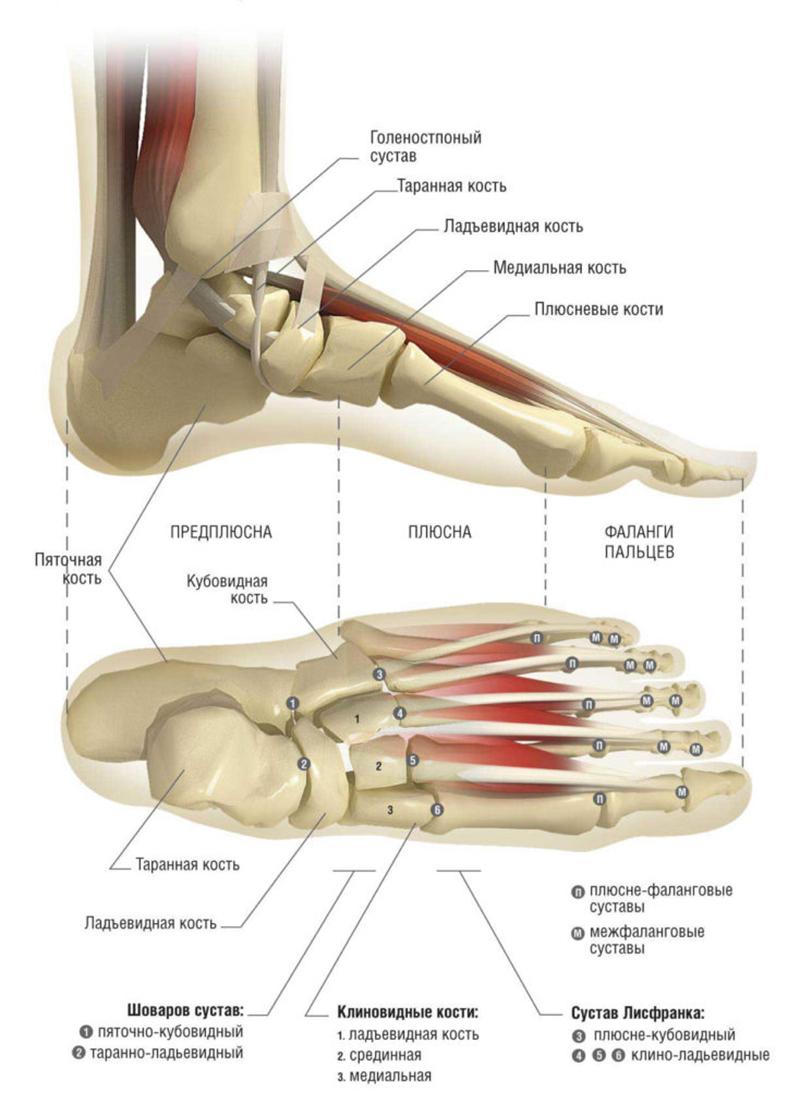

Кости голеностопа

Кости голеностопного сустава – малоберцовая и большеберцовая. К ним снизу присоединяется таранная. Под последней находится пяточная кость. Образовавшееся формирование выглядит как блок (это форма голеностопного сустава), в котором выделяют отдельные компоненты: наружную (внешнюю) и внутреннюю лодыжки и дистальную поверхность большеберцовой кости.

Каждая структура содержит места для присоединения связок и фасций, углубления для прохождения кровеносных сосудов. Фото с описанием костей дают наиболее полную информацию о дополнительных формированиях, которые на них находятся.